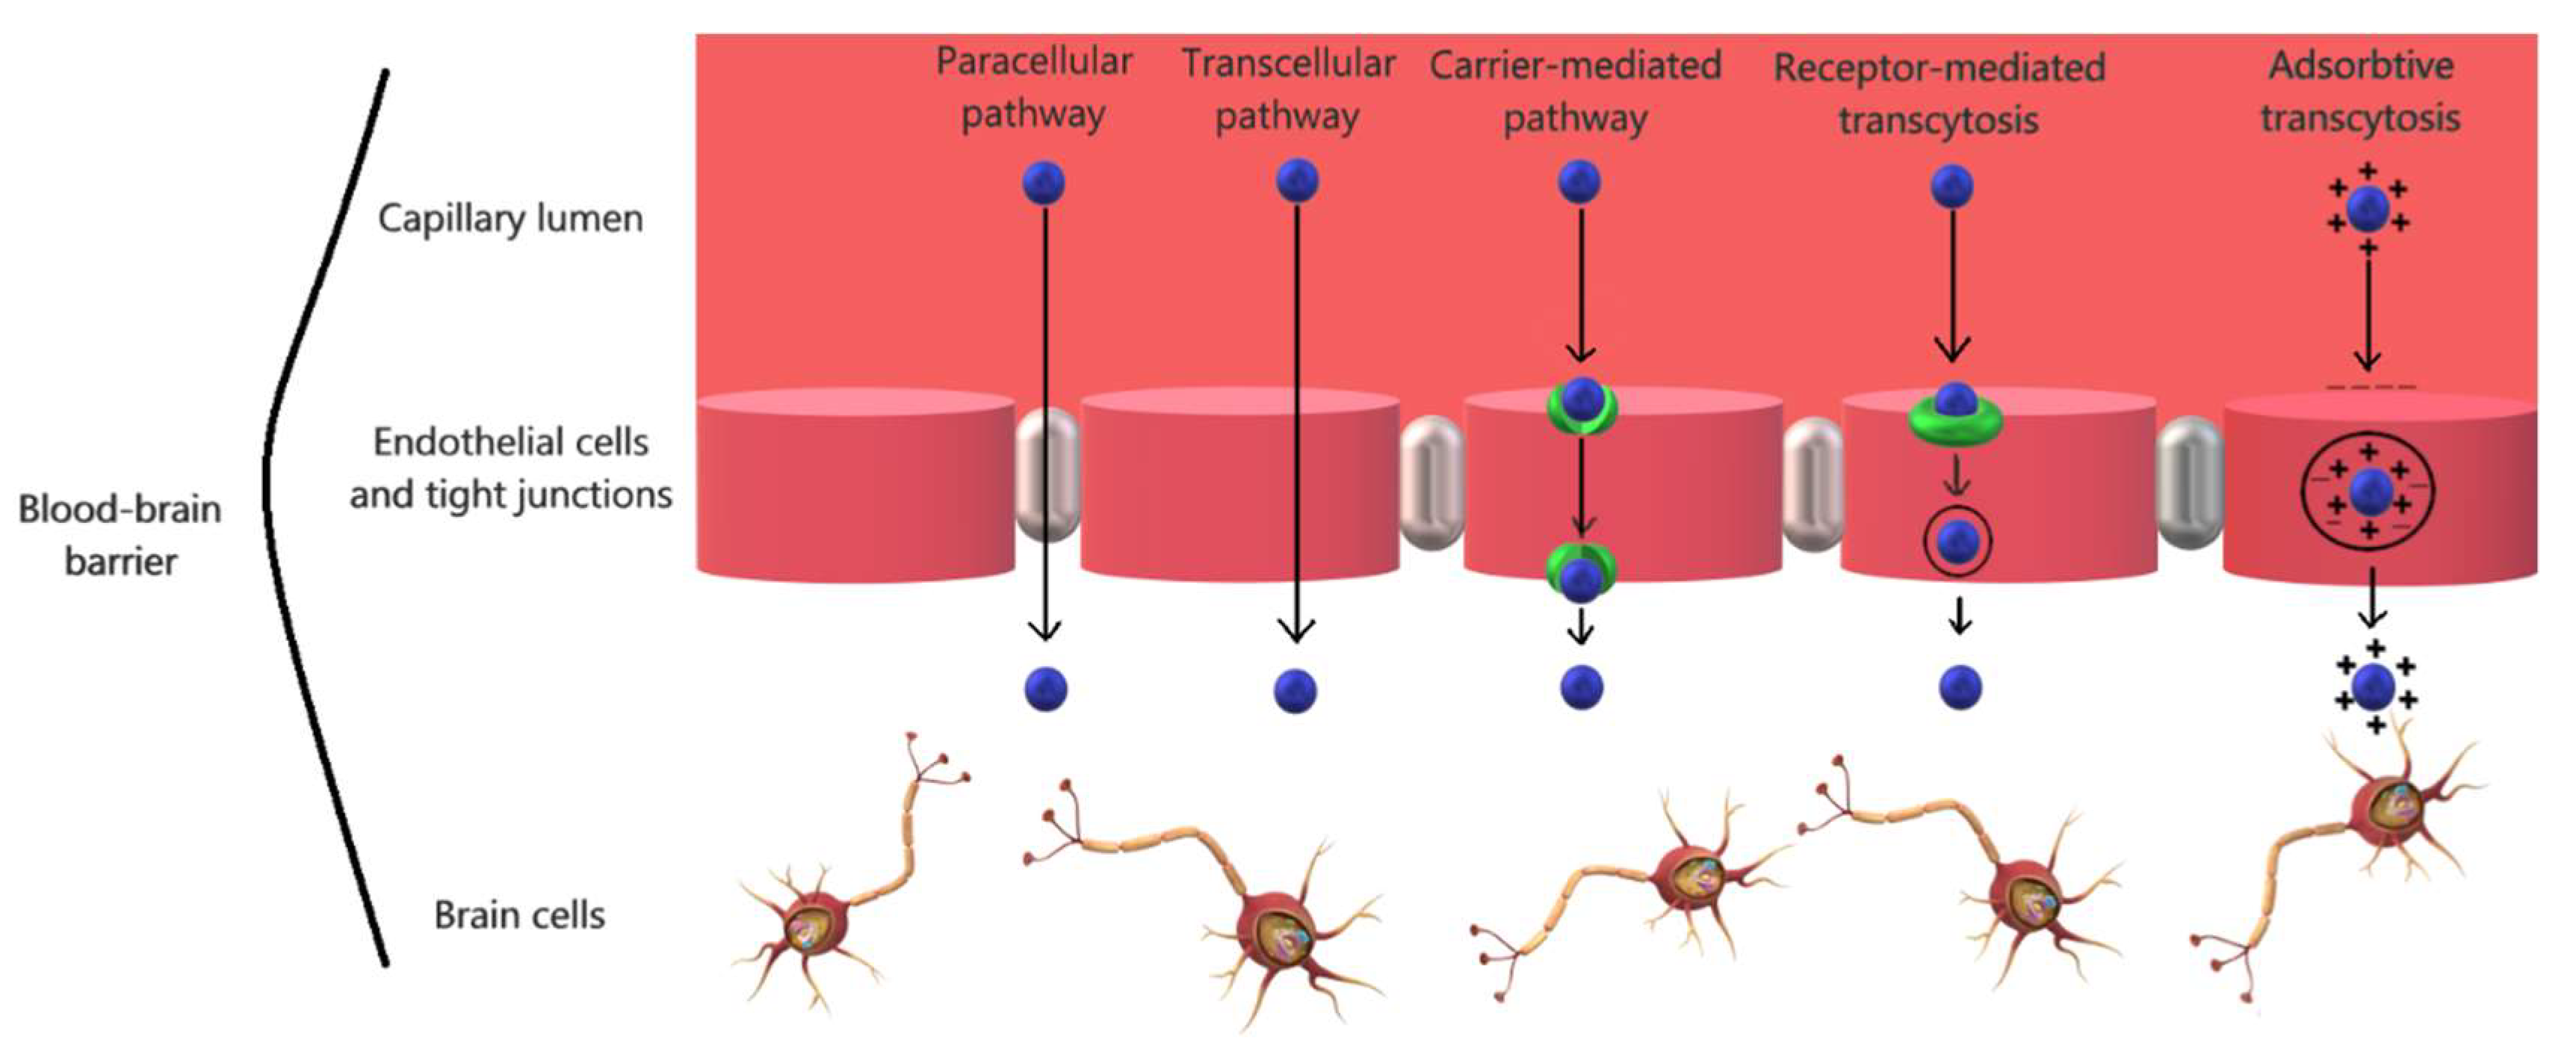

2.2. The Physiology of the Blood-Brain Barrier

3. Nanotechnology Approaches for Crossing the Blood-Brain Barrier